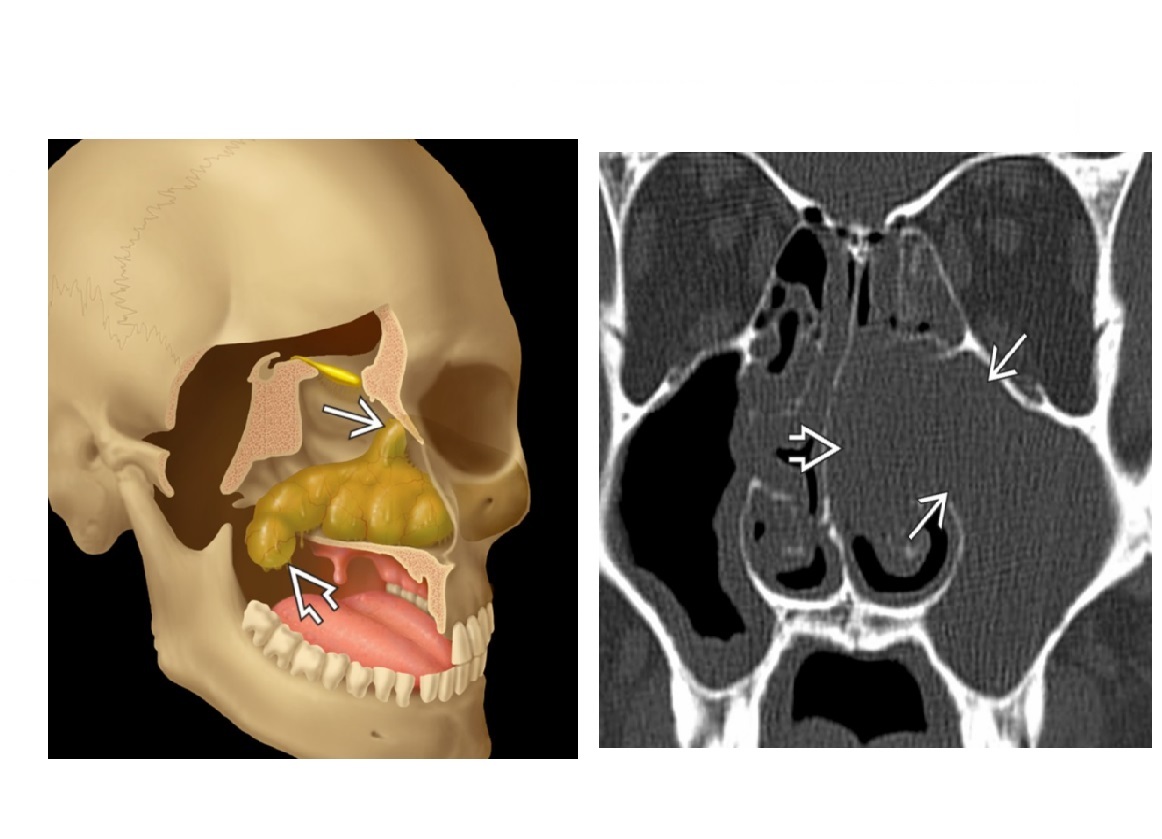

What is a Pott puffy tumour?

during acute sinusitis, bony erosion and subperiosteal abscess formation. Causes forehead swelling and can have intracranial extension.